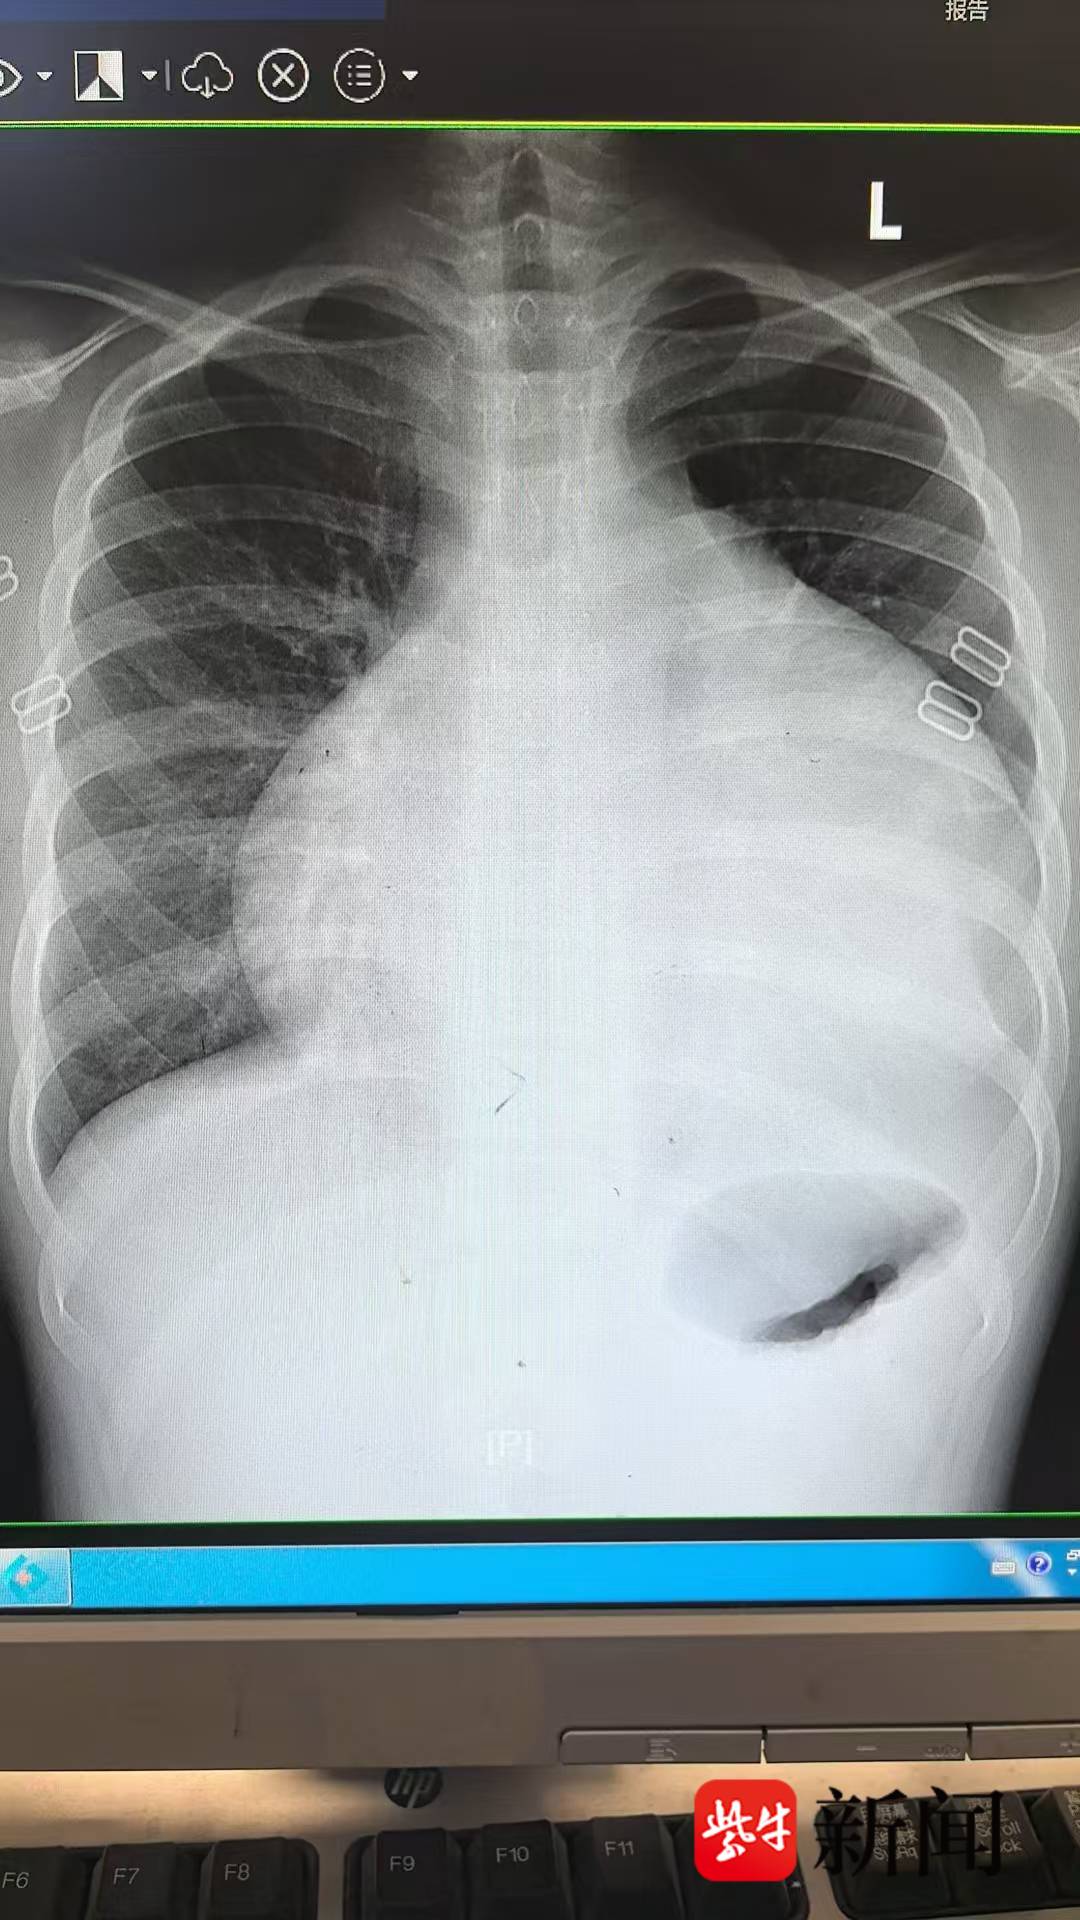

12岁的小新因持续咳嗽一周,在地方医院治疗无效后,被母亲带至常州市儿童医院呼吸科就诊。胸片检查显示其心影明显增大,进一步心脏超声提示存在大量心包积液,已压迫心脏,影响正常泵血功能。患儿随即出现胸闷、气促等症状,情况危急。

心脏中心副主任张伟团队立即为小新实施心包穿刺引流,共引出积液近3000ml,暂时缓解心脏压迫。然而,影像检查进一步发现其心脏表面存在多发性占位病变,呈“葡萄串”状附着,严重压迫大血管及气管,手术切除成为唯一有效的治疗途径。